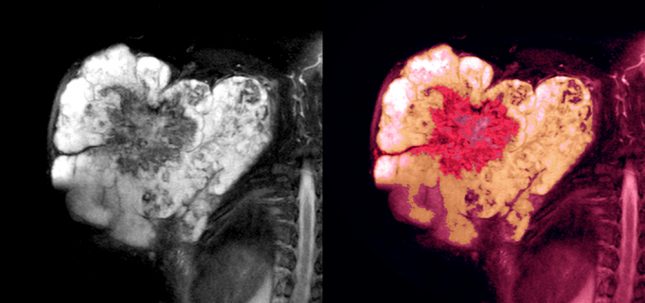

Dermatofibrosarcoma Protuberans – DFSP – מתוארת כסרקומה העורית הנפוצה ביותר. זוהי ממאירות נדירה, גדלה באיטיות, ובדרגה התמיינות נמוכה היא מראה אגרסיביות מקומית ובעלת קצב הישנות גבוה אך פוטנציאל גרורתי נמוך. רוב גידולי ה-DFSP מופיעים על פלג הגוף העליון, על הגפיים פרוקסימליות, אזורי הראש והצוואר. DFSP מאופיין באגרסיביות מקומית ואם לא הוסר לחלוטין, הוא חוזר בקלות.

קבוצת רופאים מפקיסטן פרסמה החודש תיאור מקרה שבו דווח על מטופל עם מסה בגודל 1 ס"מ על חצי ס"מ שיצאה מהחלק השמאלי העליון של ההומרוס. המטופל הופנה למנתח משחזר לאחר לקיחת היסטוריה ובדיקה גופנית מפורטות. לאחר ביופסיית כריתה, התוצאות ההיסטופתולוגיות חשפו כי הנגע היה DFSP.

הרופאים מדגישים כי נגע נדיר זה ניתן להזנחה בקלות או במקרים מסוימים ניתן לבלבל אותו עם נובוס או ליפומה, במיוחד על ידי רופאים בקהילה הממלאים תפקיד חשוב מאוד במניעה ואבחון מוקדם של נגעים טרום סרטניים. מסיבה זו יש להקפיד להעלות חשד לסרקומה עורית גם במקרים הנראים כשפירים ושכיחים.